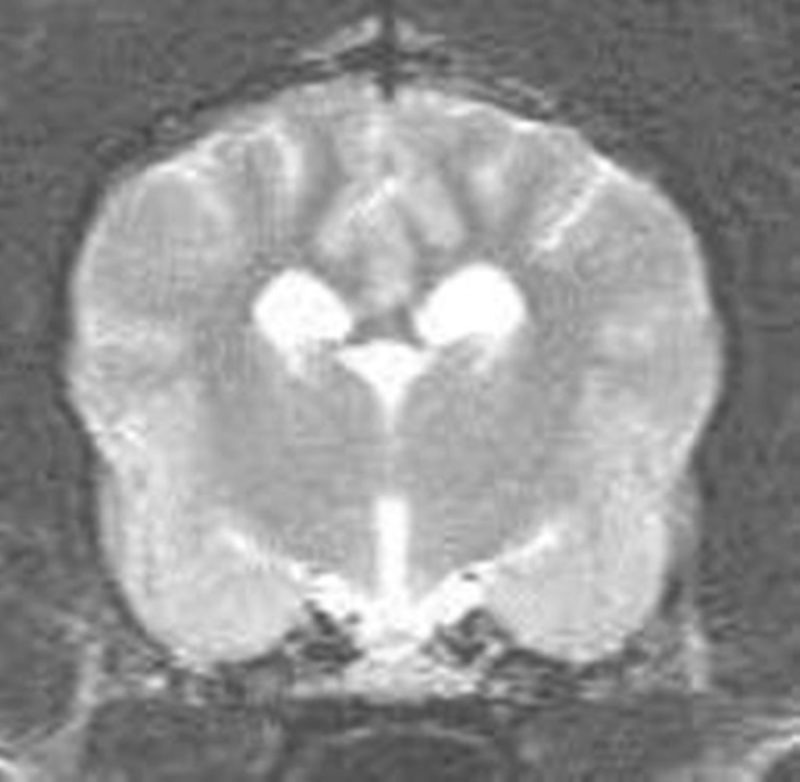

Skip wurde ausführlich körperlich untersucht, besonderes Augenmerk wurde auf die neurologische Untersuchung, vor allem seine Reflexe gelegt (Bild 1 und 2). Diese Untersuchungen verliefen absolut unauffällig. Es bestand kein Verdacht auf eine Funktionsstörung irgendeines Organs, die die Anfälle hätte erklären können. Die Befunde der allgemeinen und neurologischen Untersuchungen wurde durch eine umfangreiche Blut-und Urinuntersuchung ergänzt. Besonders wichtig ist die Überprüfung der Leberfunktion durch die Messung des Blutammoniaks, da eine Leberfunktionsstörung einerseits Ursache epileptischer Anfälle sein kann, andererseits die Medikamente zur Bekämpfung von Krampfanfällen häufig über die Leber verstoffwechselt werden müssen. Bei Skip waren alle Werte absolut normal. Eine weitere Abklärung möglicher Ursachen einer Epilepsie ist jetzt nur noch in Narkose möglich und beinhaltet die Kernspintomographie (MRT) und eine Hirnwasseruntersuchung. Nun besagt eine Studie aus Hannover, dass Hunde wie Skip, die beim ersten Anfall jünger als 6 Jahre waren und bei denen alle Voruntersuchungen bisher unauffällig verliefen, in 10% der Fälle eine krankhafte Veränderung des Gehirns aufweisen. Bei älteren Hunden liegt dieser Anteil mit 25% deutlich höher. Die Besitzer von Skip wollten auch die letzten 10% der Zweifel an einer idiopathischen Epilepsie ausschließen. Daher ließen sie die noch fehlenden Untersuchungen durchführen. Das MRT konnte keine strukturellen Veränderungen im Kopf nachweisen und das Hirnwasser enthielt keine Hinweise auf eine Entzündung des Gehirns. (Bild 3)